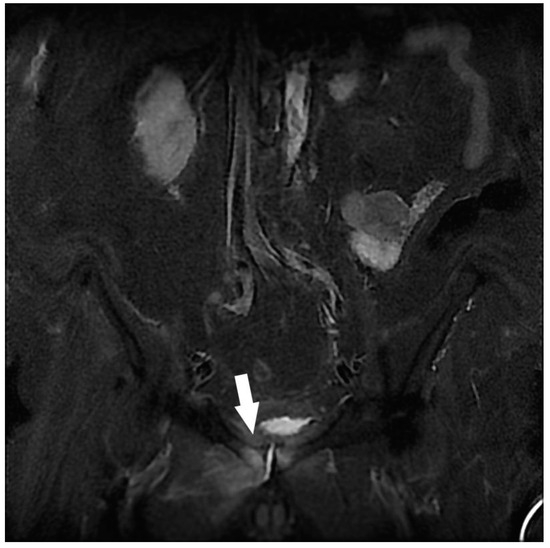

| Hip Joint | Congestive hip osteoarthritis | 17 |

| Stress femoral fracture | 4 | |

| Avascular femoral osteonecrosis | 1 | |

| Extensive acetabular edema | 1 | |

| Osteoarticular | Congestive hip osteoarthritis 2 | 8 |

| Severe hip dysplasia 2 | 1 | |

| Avascular femoral osteonecrosis 2 | 1 | |